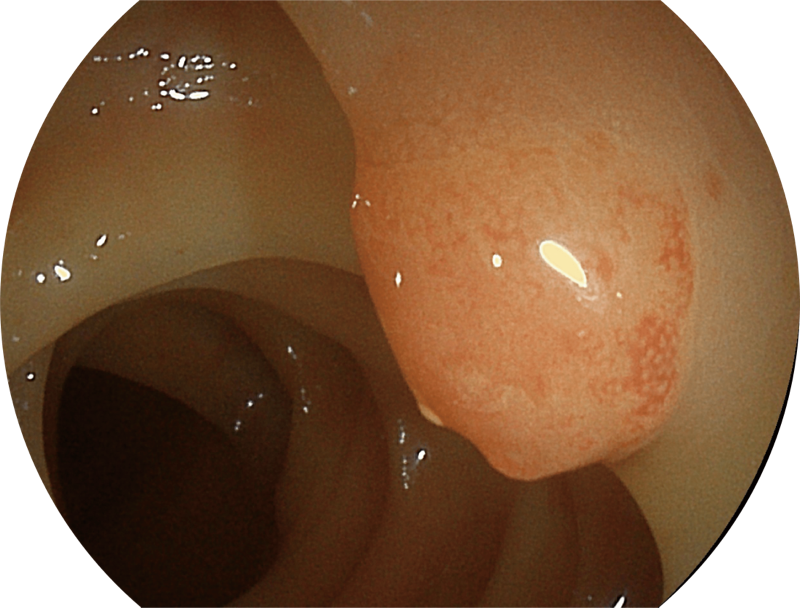

能够凸显黏膜浅层和中层血管轮廓,适用于中、远景观察下的病灶识别和早癌筛查。